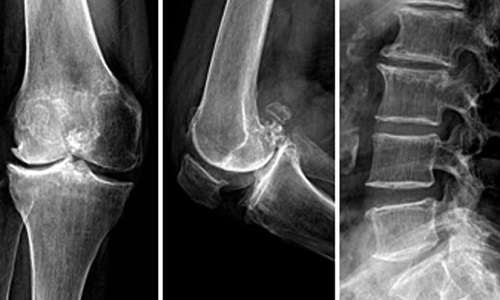

约半数患者出现关节疼痛肿胀、关节积液。以膝踝关节受累多见,尚可累及肘腕、掌指关节和跖趾关节,一般呈不对称性,疼痛以夜间为主,表现为关节轻度酸痛乃至剧烈疼痛。体征包括关节局部发红、发热、触痛肿胀、关节积液和活动受限,也有表现为无痛性关节积液。在没有大量肌肉复盖的部位,由于长骨骨膜新骨形成,可致前臂或小腿日益增粗,腕及踝关节亦相应粗大。

骨改变包括骨膜水肿、炎细胞浸润,随后有骨膜增厚、骨样基质沉着、矿化、新骨形成,骨皮质因与骨膜新生骨连接在一起而增厚。